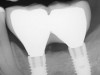

Similar to natural teeth, measurements of PPD and BoP before and after treatment are clinical parameters often used to determine the health of dental implants (Figure 4 and Figure 5). However, due to the difference between periodontal and peri-implant anatomy, concerns have been raised about the use of probes in peri-implant tissues around dental implants. These include the risk of peri-implant tissue damage,17,18 risk of damage to the implant surface by the metallic probe,19-21 risk of bacteria inoculation,22-27 and risk of galvanic corrosion resulting from contact between two dissimilar metals.21,28-30 These risks are discussed in the following sections.

Fig 4. Increased probing depth around an implant with BoP indicates presence of peri-implant disease and the need for taking a radiograph.

Figure 4

Fig 5. Bone loss shown on radiograph confirms the presence of peri-implantitis and peri-mucositis.

Figure 5